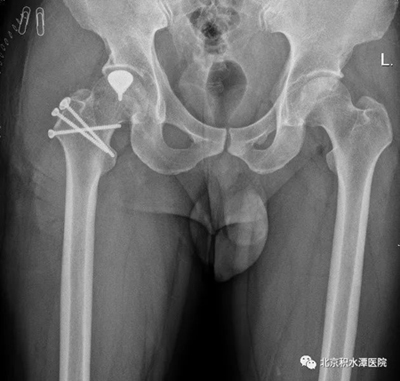

▲患者术前影像学资料显示右股骨头坏死,坏死区部分塌陷,但关节间隙正常,尚无明显骨关节炎

本次进行手术的两名患者均为年轻男性,其中小昭(化名)仅20岁左右,还是父母的心头肉。门诊通过髋关节X光,CT及MRI检查发现,小昭髋关节股骨头坏死,坏死区已经塌陷,但关节间隙正常,尚无明显骨关节炎表现。同时患者年轻,要求尽可能保留健康骨质。周一新教授团队通过对病情的综合判断,除了提供全髋置换等传统治疗选择之外,给了患者另一个选择——定制部分髋关节置换术。在充分沟通各种治疗选择的优劣后,小昭及家属决定选择定制部分髋关节置换术这一创新术式。